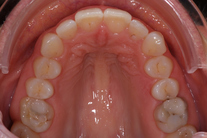

Tandreglering 4

40-årig kvinna som tycker att de två framtänderna står ut framför alla andra tänder. Behandlingen bestod av 11 månader med genomskinliga Invisalignskenor.